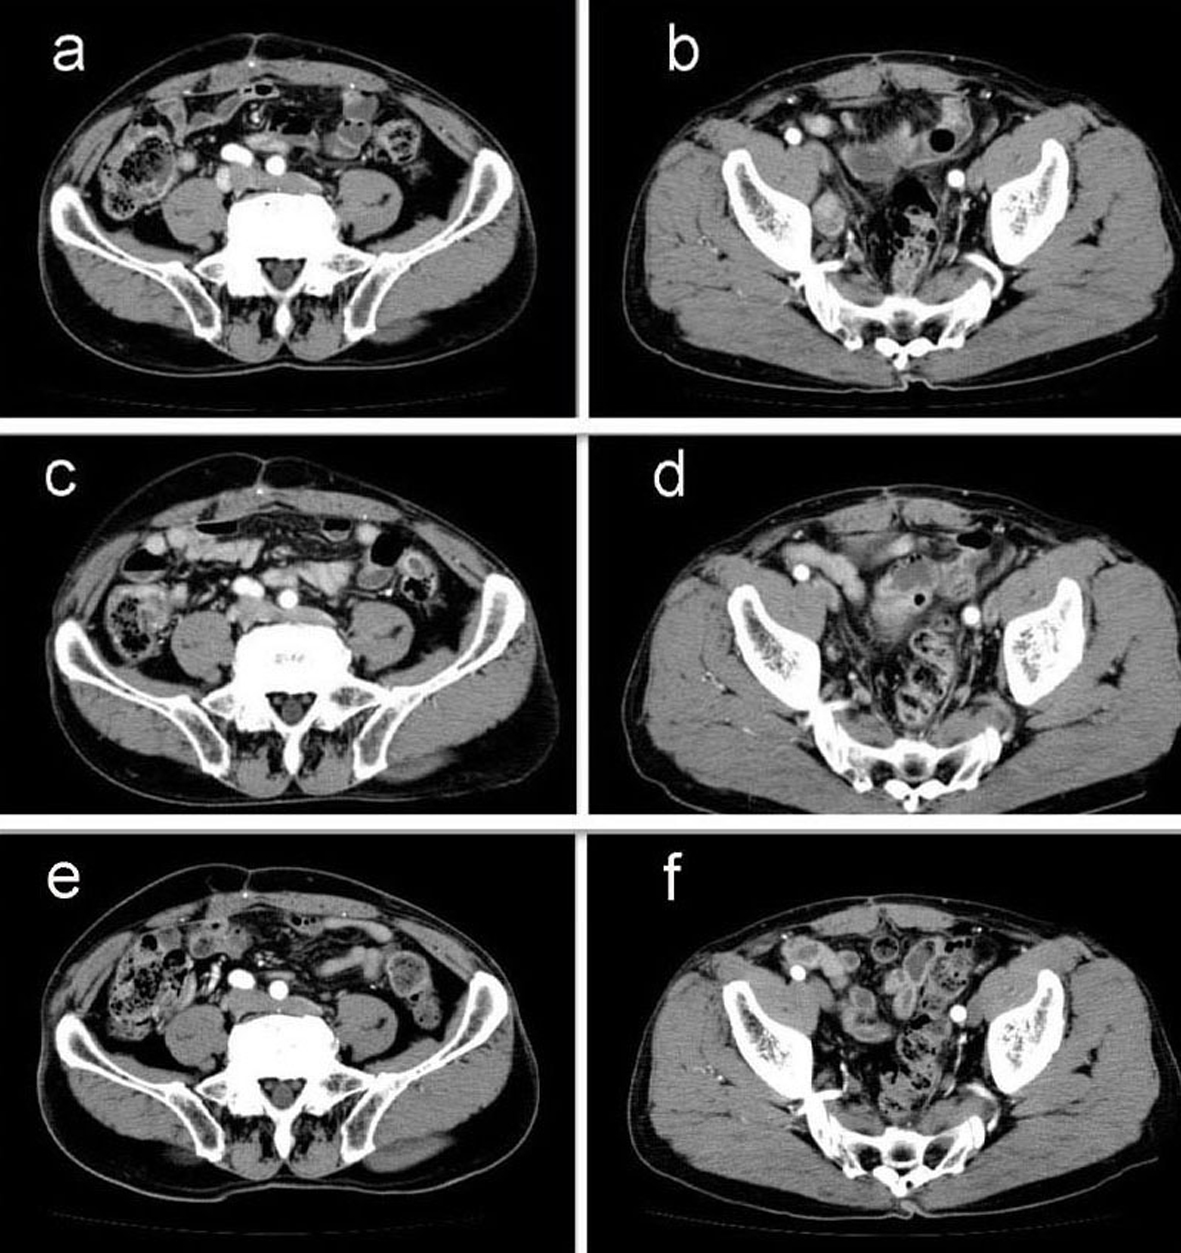

A 69-year-old man with mild liver dysfunction due to chronic type C hepatitis, underwent low anterior resection for rectal cancer in 2007. Pathological examination showed a well-differentiated adenocarcinoma invading the perirectal tissues, with metastatic involvement in 1 of the 15 lymph nodes removed (T4 N1M0/Stage IIIB), (Fig. 1). The patient underwent 5 cycles of tegafur-uracil plus oral leucovolon therapy (UFT/LV) as adjuvant chemotherapy without any adverse events. In 2008, abdominal computed tomography (CT) after UFT/LV showed swollen para-aortic and right lateral pelvic lymph nodes (Fig. 2a, b). Thus, para-aortic and pelvic lymph nodes recurrence of rectal cancer was diagnosed. We started a FOLFOX-4 regimen in March 2008. However, the patient experienced G4 neutropenia and G3 fatigue (according to the Common Terminology Criteria for Adverse Events Version 4.0), and therefore had to discontinue FOLFOX-4. We started S-1 administration (100 mg/day twice on days 1 - 14, every 3 weeks) as salvage treatment in May 2008. Abdominopelvic CT after 5 cycles of S-1 showed reduction of the swollen para-aortic lymph nodes (Fig. 2c, d).

![]() Click for large image | Figure 2. Abdominal computed tomography (CT) findings. a-b): CT scan before chemotherapy showing swollen para-aortic and right lateral pelvic lymph nodes; c-d): CT scan after 5 cycles of S-1 administration showing reduction in the swollen para-aortic lymph nodes; e-f): CT scan after radiation and 10 cycles of S-1 administration showing complete disappearance of swollen para-aortic and lateral pelvic lymph nodes. Hence, response in this case was classified as a complete response. |

Another series of abdominal CT performed after 10 cycles of S-1 monotherapy showed complete disappearance of swollen para-aortic and lateral pelvic lymph nodes (Fig. 2e, f). Hence, response in this case was classified as a CR. The patient did not experience any adverse events during the S-1 monotherapy. No signs of recurrence or metastasis were noted 36 months after CR was confirmed.